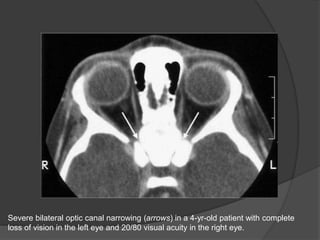

Severe bilateral optic canal narrowing (arrows) in a 4-yr-old patient with complete

loss of vision in the left eye and 20/80 visual acuity in the right eye.

Severe bilateral opticcanal narrowing (arrows) in a 4-yr-old patient with complete loss of vision in the left eye and 20/80 visual acuity in the right eye.